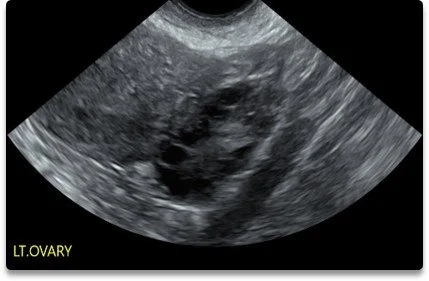

Some of the reasons why we do a pelvic ultrasound include Post Menopausal Bleeding (PMB), Intra Uterine Contraceptive Device (IUCD/Mirena) positing, Polycystic Ovaries (PCOS) and Pelvic Pain, to name a few.

30 Min

Comprehensive fertility ultrasound including antral follicle count (AFC) and assessment of uterine and ovarian health. This scan provides important baseline information for your fertility journey. -